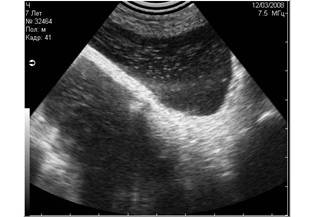

![]() |

Рис. 11. Истинные тени, испускаемые скелетными структурами плода шелти на 36 день беременности. Первичными очагами минерализации являются череп и таз плода. На этом снимке мы видим две тени, испускаемые этими структурами. |

Рис. 12. Истинные эхоакустические тени, испускаемые уплотнёнными стенками сосудов при гепатозе (фиброзе). |